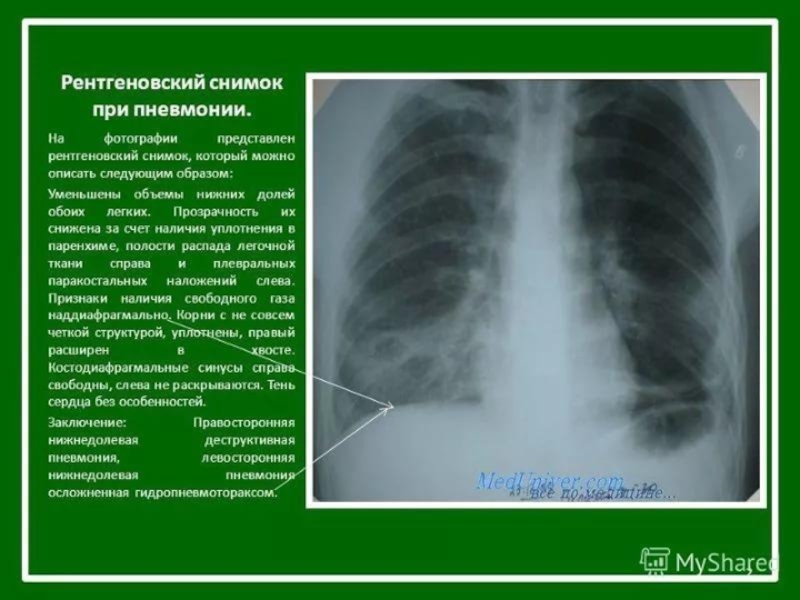

Рентгенологические признаки пневмонии – рентгенография является наиважнейшим и

незаменимым методом исследования для подтверждения клинического диагноза пневмонии.

При подозрении на пневмонию рентгенография грудной клетки выполняется в двух проекциях: прямой и боковой проекциях. Типичным рентгенологическим признаком пневмонии является затемнение легочной ткани, которое может быть очаговым, сливным, сегментарным (полисегментарным), долевым или еще более распространенным (тотальным). Изменения на рентгенограмме (распространенность инфильтрации, наличие или отсутствие плеврального выпота, полостей деструкции) указывают на тяжесть заболевания, помогают в выборе антибактериальной, симптоматической и другой (например, плевральная пункция) терапии.

Рентгенография органов грудной клетки. Рентгенологически характерным для крупозной пневмонии является гомогенное затемнение той или иной доли, или ее сегментов. При очаговой пневмонии у большинства больных выявляются очаговые тени средней или малой интенсивности, часто с неровными контурами.